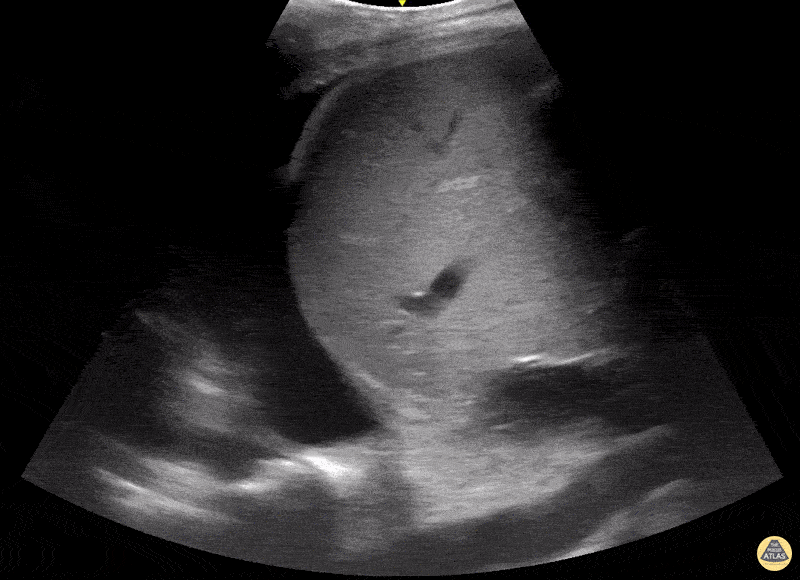

Pulmonary - Pleural Effusion with Compressed Lung and Spine Sign

Pleural effusion with compressed lung and positive spine sign Contributed by: Dimitri Livshits DO, Ultrasound Fellow; Jane Belyavskaya MD, Ultrasound Fellow; Chris Hanuscin MD, Ultrasound Division Director (Kings County/SUNY Downstate)